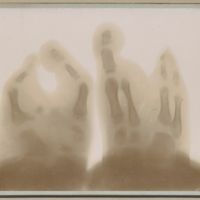

0003 - Page 2 - Tâtonnements du début - Deuxième impression de la plaque, après 10 minutes de pose, le tube restant fixe0003 - Page 2 - Tâtonnements du début - Deuxième impression de la plaque, après 10 minutes de pose, le tube restant fixe